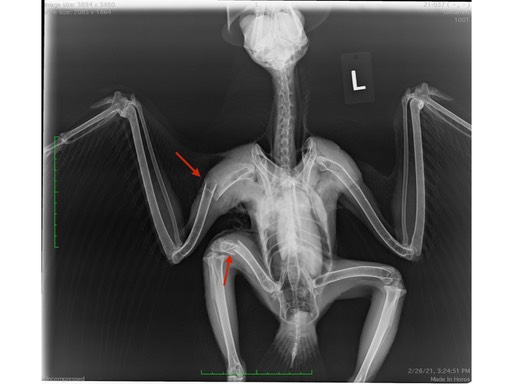

Two of the Red-tailed Hawks had both humerus and femur fractures. One was shot, the other was hit by a car. In the first radiograph the arrows point to damage caused by one projectile. If you look closely, you will see a tiny metal fragment at the tip of arrow one. Many metal fragments and a humerus fracture are visible at arrow 2. Although there are no metal fragments visible at arrow 3, necropsy results indicated the projectile was responsible for the femur fracture. The arrows in the second radiograph point to the humerus and femur fractures caused by the bird being struck by a vehicle.